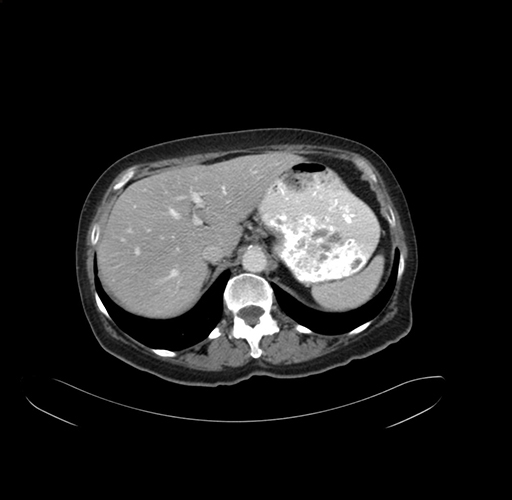

Axial Venous